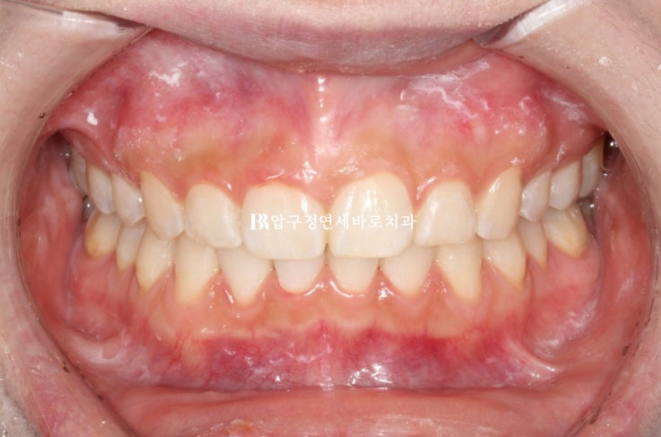

24년 8월부터 12월까지 두 번째 세트의 추가장치를 다 낀 후 24년 12월 치료를 마무리 했습니다.

24.12

중심선이 잘 맞습니다.

거미스마일을 고치느라 위 앞니를 함입 시켜서 잇몸이 치아를 많이 덮어 치아 높이가 짧아졌습니다.

이제 교정은 끝났으니 잇몸성형으로 잇몸 라인을 다듬어 줍니다.

좌 - 치료 전 우 - 치료 후

22.09~24.12

유지장치까지 들어간 모습입니다.

거미스마일 개선이 눈에 띕니다.

돌출감만 해소된 과하지 않은 적당한 입매

발치 공간으로 어금니 쓰러짐 없이 뿌리까지 평행하게 이동 된 것이 확인됩니다.